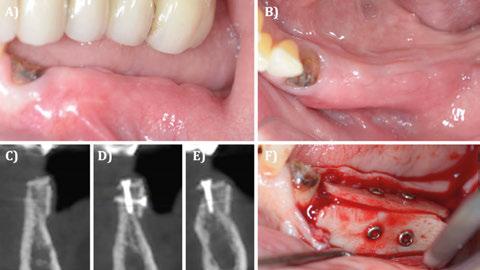

4.2.2. Injerto óseo alogénico (Figuras 28-31)

Los injertos óseos de origen alogénico presentan propiedades biológicas como la osteoinducción y la osteconducción y, por eso, investigaciones recientes los proponen como una alternativa válida y con menor morbilidad que los injertos autólogos (Park y cols 2017, Spin-neto y cols 2015, Silva y cols 2017, Tunkel y cols 2021, Regidor y cols 2021). Por el contrario, este tipo de injertos óseos no tienen capacidad osteogénica y, por eso, la formación de hueso requerirá de

mayor tiempo de espera y podría incluso resultar en una cantidad menor de hueso neoformado (Chiapasco 2015a; Chiapasco 2015B; Stavropoulos y cols 2023).

Los estudios que analizan la ganancia ósea horizontal y vertical tras el uso de aloinjertos óseos reportan una ganancia media de 4.79 mm (Monje, Nikos, Chan y cols 2014) y 4.03 mm (Macedo y cols 2012), respectivamente. En relación con el hueso neoformado tras el uso de aloinjertos, los resultados reportados por las investigaciones oscilan entre el 32 y 58% de la muestra, siendo un 15-40 injerto óseo residual y un 1954% tejido conectivo (Acocella y cols 2012; Ahmadi y cols 2017; Aslan y cols 2016 y Chaushu y cols 2019).

Figura 28. Caso clínico tratado mediante injerto óseo de lámina alogénica (Cortical Plate Salugraft®). A) Situación clinical basal. B) Situación radiográfica (3D) basal en posición de 45. C) Situación radiográfica (3D) basal en posición de 46. D) Extracción de 45 y elevación del colgajo a espesor total. E) Fijación de las láminas alogénicas (Cortical Plate Salugraft®) vestibular y oclusal.

Figura 30. Caso clínico tratado mediante injerto óseo de lámina alogénica. Continuación. A) Vista vestibular tras 4 meses de cicatrización. B) Vista oclusal tras 4 meses de cicatrización.

C) Vista transversal radiográfica (3D) en posición de 44. D)

Vista transversal radiográfica (3D) en posición de 45. E) Vista transversal radiográfica (3D) en posición de 46. F) Reentrada tras 4 meses del procedimiento quirúrgico.

Figura 29. Caso clínico tratado mediante injerto óseo de lámina alogénica (Cortical Plate Salugraft®). Continuación. A) Vista vestibular de la lámina vestibular. B) Vista oclusal de la lámina oclusal con un injerto de tejido conectivo autólogo en la zona de la extracción. C) Sutura y cierre primario del procedimiento. Vista oclusal. D) Sutura y cierre primario del procedimiento. Vista vestibular.

Figura 31. Caso clínico tratado mediante injerto óseo de lámina alogénica. Continuación. A) Colocación de los implantes. Vista oclusal. B) Vista oclusal del cierre primario tras el procedimiento de colocación de implantes. Cicatrización no sumergida.

C) Radiografía (2D) inmediata postoperatoria tras la colocación de los implantes. D) Colocación de la prótesis implantosoportada 3 meses después de la colocación de los implantes.